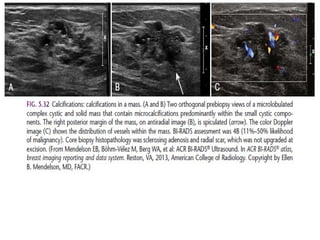

Microlobulated. This implies a suspicious finding.

Suspicious morphology

Amorphous (BI-RADS 4B)

So small and/or hazy in appearance that a more specific particle shape cannot

be determined.

Coarse heterogeneous (BI-RADS4B)

Irregular, conspicuous calcifications that are generally between 0,5 mm and 1

mm and tend to coalesce but are smaller than dystrophic calcifications.

Fine pleomorphic (BI-RADS 4C)

Usually more conspicuous than amorphous forms and are seen to have discrete

shapes, without fine linear and linear branching forms, usually < 0,5 mm.